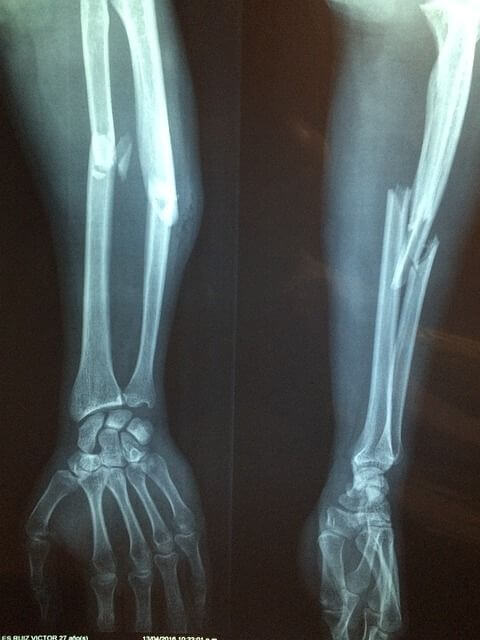

초기 키엔벡병은 단순 방사선촬영(엑스레이)으로 진단할 수 없습니다. 키엔벡병이 진행되면 XR로도 확인할 수 있습니다. 초기에는 MRI를 통하여 진단할 수 있습니다.

키엔벡병은 경과에 따라 1-4기로 나뉩니다. 1기는 XR상 정상소견이나 MRI에서 무혈성괴사 소견을 볼 수 있습니다. 2기의 경우 XR에서 골경화의 소견이 보이고, 월상골이 경미하게 붕괴될 수 있으나, 주변 작은 뼈는 잘 유지되는 단계입니다. 3기의 경우, 월상골의 파괴가 일어나며, 주상골의 회전이 있는지 없는지를 따라 A.B형으로 나뉩니다. 4기의 경우, 손목 전체에 퇴행성 관절염 소견과 함께 월상골의 붕괴가 심하게 일어난 단계입니다.